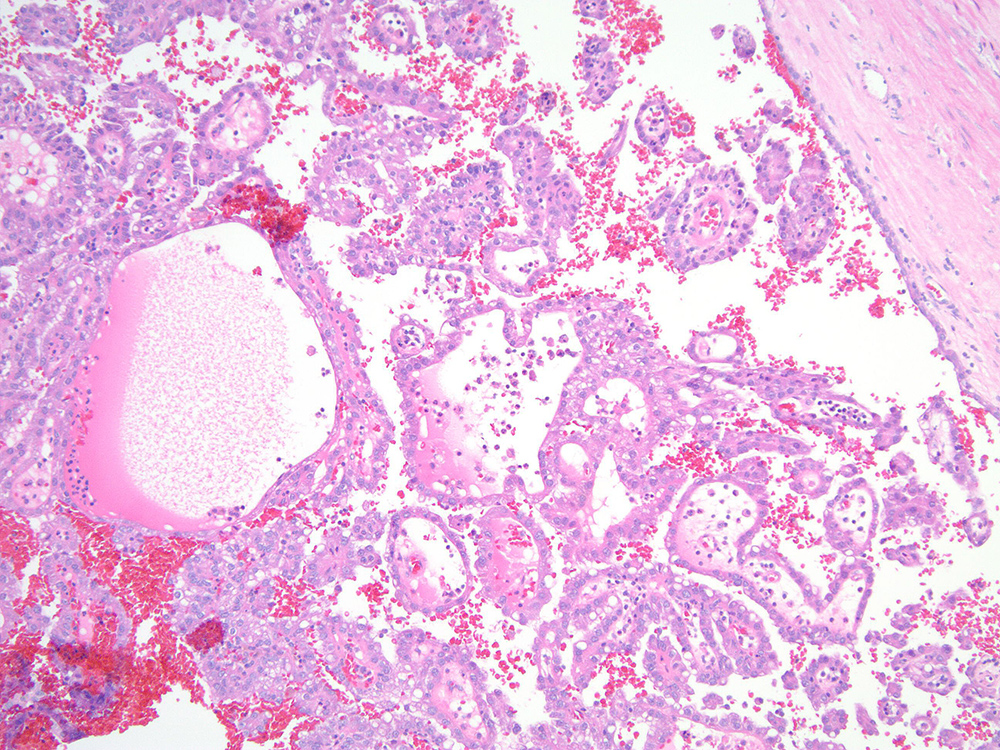

Renal tumor grading

Case ID: 713